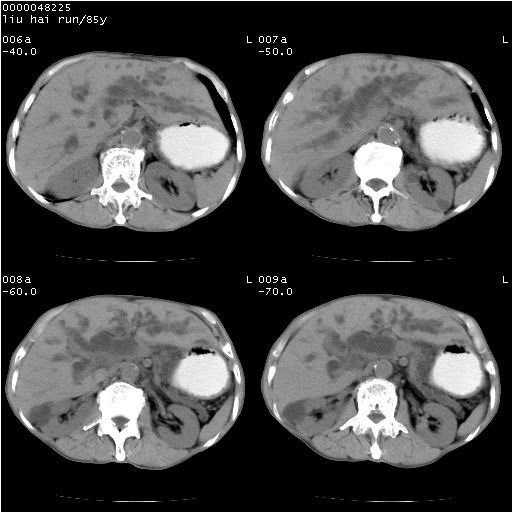

标题: CT13403:M,85Y。胆系低位梗阻。胰头占位? [打印本页]

标题: CT13403:M,85Y。胆系低位梗阻。胰头占位?

彩超示胰头实质欠均匀,胰管扩张。

有“双管征”,胆总管胰头段突然中断,考虑为胰头癌。

影像表现:壶腹部扩张胆管呈截断样改变,肝内外胆管重度扩张,胆囊增大,胰管亦明显扩张,呈不规则患珠样,胰体尾部略有萎缩,增强扫描后壶腹部低密度影轻度强化,与钩突分界不清。

ct诊断:胆管癌。鉴别诊断:胰腺癌,胰腺癌为少血供肿瘤,增强后强化不明显,静脉期及延时后与正常胰腺分界清晰。

双肾多发囊肿

胆总管下端突然截断,胰腺萎缩,胰管扩张,肝内外胆管扩张,考虑胆总管下端癌可能性大。不除外胰腺钩突占位。

1)胆系低位梗阻(肝内外胆管扩张、胰管扩张、胆囊增大);考虑为:胰头癌可能性大,不排除胆总管下端癌。2)双肾多发囊肿。